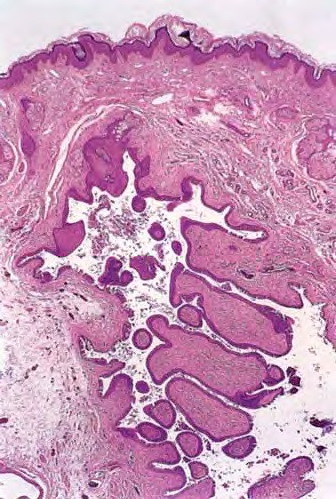

Bronchogenic cysts are lined by a mucosa consisting of ciliated pseudostratified columnar epithelium . Goblet cells may be interspersed. The wall frequently contains smooth muscle and mucous glands but only rarely contains cartilage